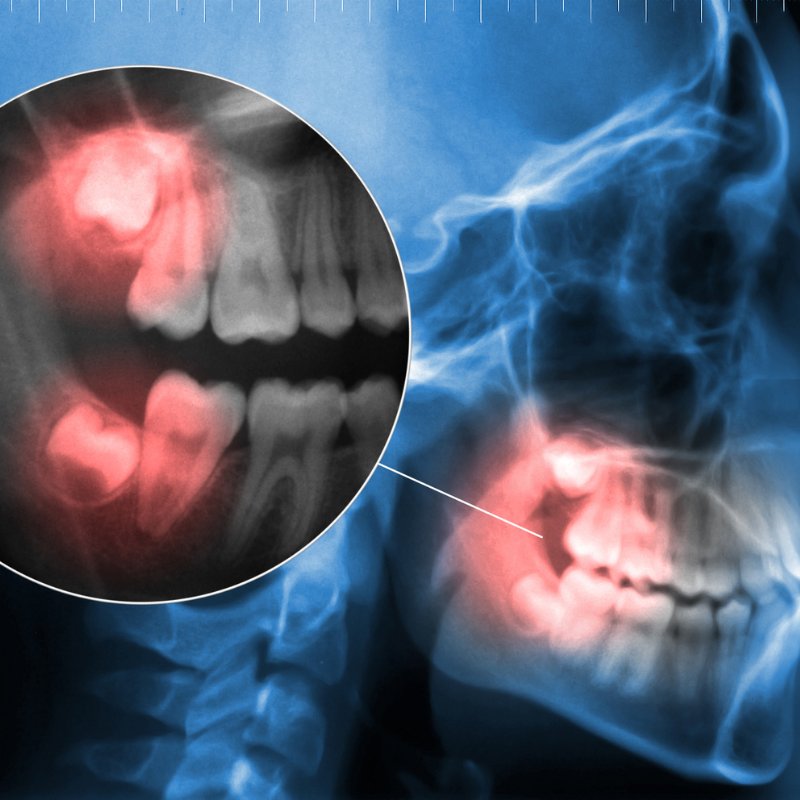

Your visit begins with a detailed evaluation using digital X-rays and 3D imaging. This helps us see the exact position of your wisdom teeth and create a precise treatment plan.